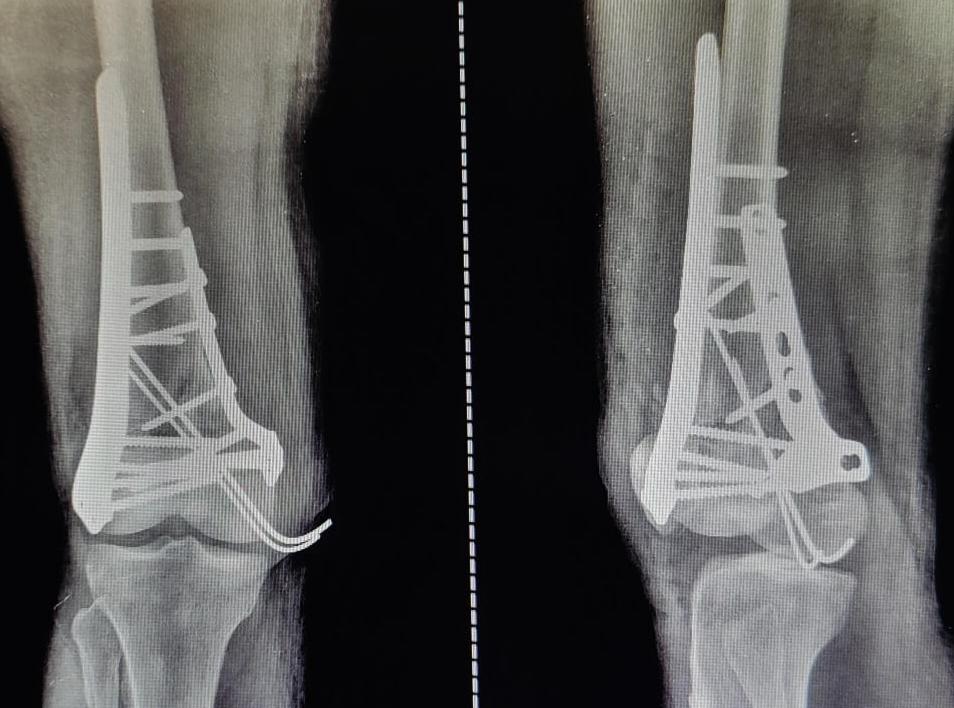

A very standard and safe approach was used to fix the fracture. All the fracture fragments were beautifully and carefully aligned together. This restored the joint line of knee joint along with cartilage lining of the knee joint.

After this step, final fixation of fracture was done using multiple plates and screws. Each step of the process of fixation of fracture is very critical for best outcome. Surgeons at Varunam Hospital are equipped with latest technology to adequately handle such fracture and give optimal results. You can consult Dr Utsav Agrawal, Orthopaedic Surgeon in Nagpur at Varunam Hospital in case you need any guidance. Click Here to Call us to book an appointment or call 7447799000.